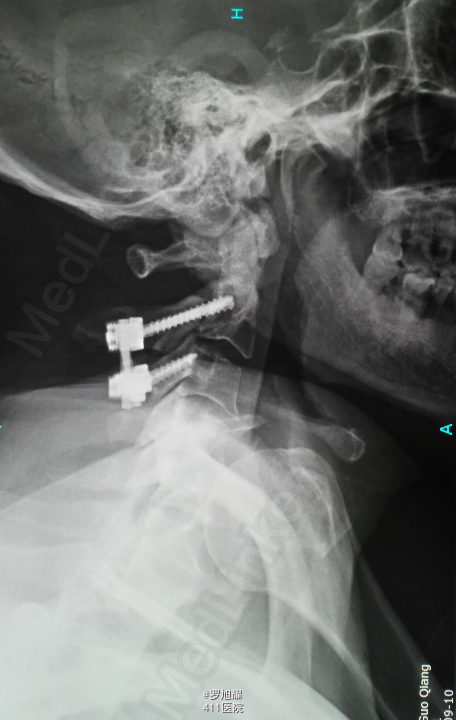

入院立即给与大剂量甲强龙冲击治疗,辅以甘露醇脱水消肿,兰索拉唑保护胃黏膜,腺苷钴胺恩经复营养神经,伤后10天复查MRI脊髓信号增高明显,两周后生命体征稳定,肢体感觉和肌力见部分恢复,行颈2椎弓根螺钉、颈3侧块钉内固定术,因神经压迫不明显未行椎板切除减压。 术后3月骨折线基本消失,患者感觉肌力几乎完全正常,右肩残留疼痛磁共振检查发现肩袖损伤,暂予局封治疗症状缓解。